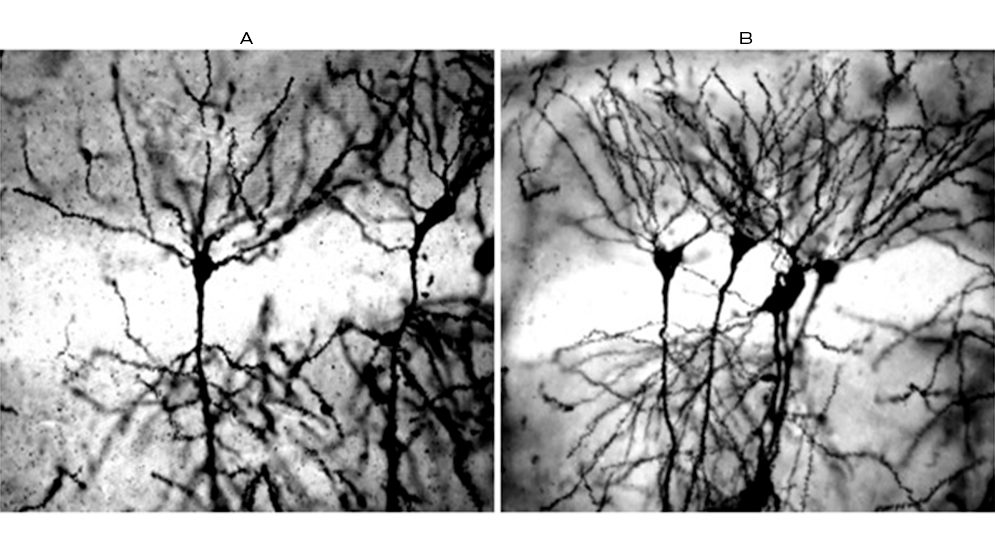

Una vez obtenido el fármaco modificado, el equipo de la UNL convocó al Laboratorio de Neurobiología Molecular y Celular que dirige la investigadora del CONICET Camila Scorticati en el Instituto de Investigaciones Biotecnológicas de la Universidad Nacional de San Martín (IIBIO, CONICET-UNSAM), para poder realizar los ensayos en neurobiología (neuroplasticidad y neuroprotección) y así validar sus efectos terapéuticos.

“Nosotros nos dedicamos a estudiar los procesos de diferenciación neuronal, formación de sinapsis y neuroprotection in vitro -en cultivo primario de neuronas- y en animales de laboratorio. Marcos nos convocó a participar en el proyecto y testear la capacidad de estas moléculas innovadoras de preservar la actividad neuroprotectiva y neuroplástica de hEPO. Y así fue que comenzó la colaboración”, comenta Scorticati. Gabriela Aparicio, entonces becaria del CONICET en el IIBIO, también se sumó al proyecto. “En aquel momento, 2017, una nota sobre el trabajo de Camila acaparó mi atención sobre las potencialidades del laboratorio que ella dirige y el gran aporte que nos podía brindar”, menciona Oggero.

Hasta el momento, el desarrollo fue probado con éxito en ensayos de neuroplasticidad y neuroprotección, tanto in vitro como in vivo (en ratones normales).